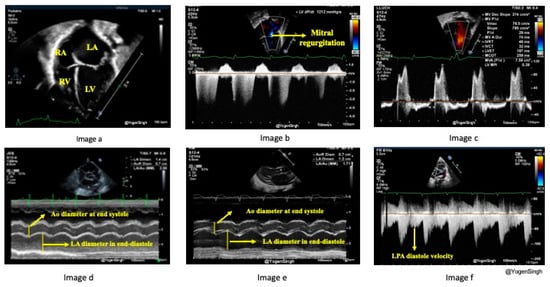

3.2. Echocardiographic Assessment of Pulmonary Over-Circulation

The increase in pulmonary blood flow caused by the PDA may not be directly measured at the bedside, but it can be estimated with surrogate echocardiographic parameters. A significant PDA shunt volume leads to turbulence in branch pulmonary arteries, especially near its insertion near LPA and increased diastolic velocity >0.42 m/s across left pulmonary artery origin is associated with an hsPDA [21] (Figure 4f). The increased pulmonary blood results in increased pulmonary venous return, leading to dilated pulmonary veins and increased pulmonary vein Doppler flow. The increased pulmonary venous return causes the LA to dilate. As the aortic valve annulus (Ao) is relatively fixed, the LA/Ao ratio is a surrogate for increased pulmonary venous return [21,22]. The mitral valve E/A ratio measures the inflow velocity during the early (E) diastolic phase of ventricular filling compared to the late atrial (A) contraction phase. Typically, the E/A ratio is >1, but in the presence of LA and LV volume overloading from the PDA shunt, this ratio is reversed, and the E/A ratio becomes <1. MV inflow (E-wave) slows down with increased LV volume and pressure, and there is an increased ‘A’ velocity from atrial contraction to push extra LA volume left after the initial diastolic phase (E-wave) (Figure 4c). Elevated LA pressure may cause early mitral valve opening or shorten isovolumic relaxation time (IVRT). The subsequent increase in LV volume can be quantified by measuring the LV end-diastolic dimension (LVEDD), adjusting to gestational age and body weight (z-score) [23]. Sometimes, the left heart dilation is noticeable enough to be visually observed as an LV/RV size discrepancy. Mitral valve insufficiency may be seen in infants with hsPDA and a significantly dilated LV [23] (Figure 4b). Higher LV volume enhances LV cardiac output (LVO) and stroke volume, which can be calculated using velocity time integral (VTI) and Ao size [24]. If there is a significant intra-atrial or intra-ventricular shunt to alleviate volume overload in the left heart, it might result in reduced or delayed left heart dilation. Without an intracardiac shunt, an hsPDA may have a higher LVO to superior vena cava (SVC) flow ratio because the SVC is the surrogate for the return volume of preductal systemic blood flow [11,21].

Many echocardiographic parameters have been described [17,21]. The commonly used in clinical practice, which offer higher sensitivity and specificity, are: increased LPA diastolic velocity, an increased LA/Ao ratio, a qualitative assessment of left heart dilatation, and increased LVEDD [17,21] (Figure 4). To measure the LPA diastolic velocity, a pulsed wave Doppler is used to interrogate LPA blood flow in the parasternal short axis view. A mean and end-diastolic velocities of >0.42 m/s and >0.2 m/s, respectively, are highly suggestive of an hsPDA with a sensitivity and specificity of >90% [21] (Figure 4f). The LA/Ao ratio can be obtained from the parasternal long-axis view or the parasternal short-axis view using an M-mode cursor across the aortic valve level and left atrium. An LA/Ao ratio of >1.4 is suggestive of an hsPDA [22] (Figure 4d,e). LVEDD can also be measured from the parasternal long-axis view with an M-mode cursor at the tip of the MV leaflet or by placing the cursor perpendicular to the mid-LV cavity at the level of the papillary muscle in the parasternal short-axis view. Measured LVEDD values higher than the normative z-score adjusted to body weight and postnatal age suggest LV volume overload and a dilated left ventricle [23]. A rapid qualitative assessment on visualization of the heart chambers in apical 4-chamber view and the parasternal long axis view can be done—a significantly dilated LA/LV compared to the RA/RV is noted on “eyeballing,” but this remains subjective and may not be precisely accurate.

Figure 4. Echocardiography assessment of pulmonary over-circulation. (a) shows the left heart is larger than the right heart due to volume overload in the apical four-chamber view. (b) shows the mitral regurgitation on color flow mapping from the apical four-chamber view. (c) shows E/A ratio inversion across the mitral valve inflow. (d) shows the increased LA to Aorta (LA/Ao) ratio in the parasternal short-axis view on the M-mode. (e) shows the increased LA to Aorta (LA/Ao) ratio on the M-mode in the parasternal long-axis view. (f) shows an increased diastolic velocity in the left pulmonary artery (LPA). LA—left atrium, LV—left ventricle, RA—right atrium, RV—right ventricle, Ao—aortic valve, LPA—left pulmonary artery.